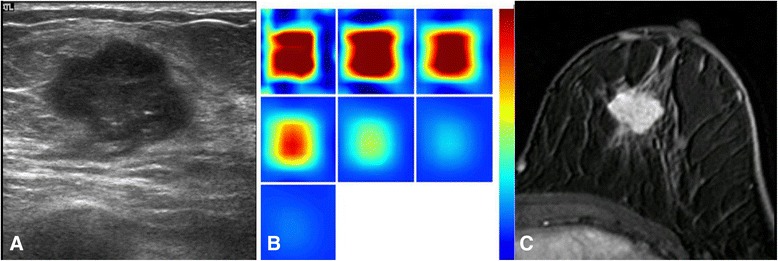

Based on the US images, a square region of interest (ROI) was drawn to include the maximal diameter and the perpendicular dimension of the lesion. Since the ROI was a square shape, it encompassed the whole area of the identified lesion and a small portion of the surrounding normal tissues. Then the optical imaging was acquired using the same hybrid probe. The plane that showed the maximal diameter of the tumor was used as the optical horizontal plane. Then, the probe was rotated by 90° angle to acquire the optical data from the vertical plane. Next, we performed the same process in the symmetric region in the contralateral normal breast, including the horizontal and vertical planes. The optical imaging measured the normal site in the symmetrical region of the contralateral breast was used as references in the reconstruction. After scanning the four planes (two lesion planes and two contralateral normal planes), the optical characteristic parameters and the total hemoglobin concentration (THC, micromoles per liter) were obtained by calculating the difference between the lesion and the symmetric normal site, and the images were displayed on the screen of the imaging system. The maximal THC value was determined as the maximal hemoglobin concentration in the region of interest box (Fig. 1a , b).

Between the THC and DCE-MRI parameters, only THC and SER showed a weak correlation with statistically marginal significance (r = 0.303, p = 0.058, Table 2). A higher total hemoglobin concentration was correlated with a more rapid washout rate (Fig. 1). There was no statistical significance in the correlation of THC and other two DCE-MRI parameters (r = −0.237 with Ktrans,p = 0.157; r = −0.218 with kep, p = 0.195). Fig. 2 illustrates one example of discordant findings between DCE-MRI and THC; while an unenhanced necrotic core is clearly noted on MRI, a high homogeneous THC map is shown on US-DOT. The mean and standard deviation value for each parameter are shown in Table 3.